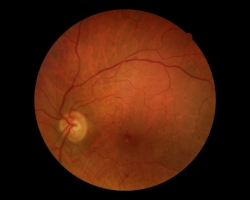

• Rétinophotographies comparatives bilatérales en 2017 et 2018

Passage d’une rétinopathie diabétique minime vers une rétinopathie diabétique modérée en 2018 avec œdème maculaire sur diabète déséquilibré

• 2017 : quelques hémorragies avec prédominance à l’œil gauche

• 2018 : même tableau en plus sévère avec beaucoup plus d’exsudats durs de résorption en rapport avec de l’œdème maculaire diabétique